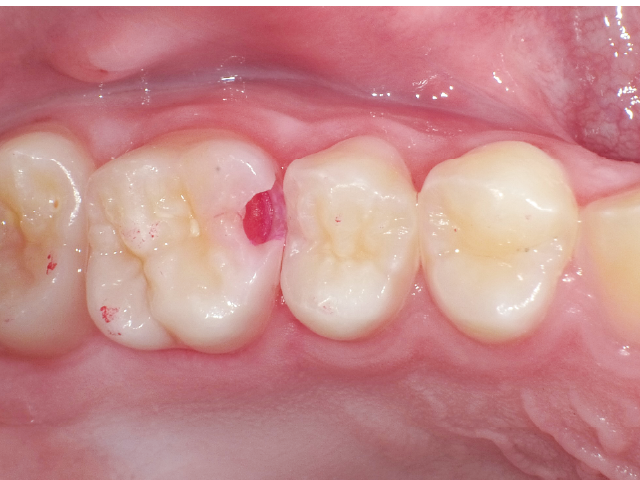

②充填段階(図10~22)

窩洞形成完了後は隣接面部健全歯質の残存範囲によりコンポジットレジンの充填時に用いるマトリックスシステムを選択していきますが、今回はシンプルな操作で設置可能なトッフルマイヤータイプのマトリックスシステムを選びました。隣在歯との距離が小さく、フラットな隣接面形態の再現が必要な症例には最適で、同時に精度の高い窩洞の防湿も可能です。使用したメタルのマトリックスバンドの厚さは30µmと非常に薄く、隣在歯との間に適切な接触関係を回復することができます。

接着操作には窩縁部エナメル質へのセレクティブエッチングに続いて、2ステップタイプのセルフエッチングシステム(クリアフィル® メガボンド®2 : クラレノリタケデンタル)を使用し、フロアブルレジンとペーストタイプレジンとを併用したシンプルな積層充填操作により隣接面形態を回復しました。

臼歯部隣接面における初期う蝕治療では、適切なタイミングで治療に介入し、充填操作の行いやすい環境で窩洞形成を終えることが、最終的な修復の長期予後を左右します。う蝕が象牙質に進行することにより、エナメル‐象牙境におけるう蝕の範囲拡大が起き、その程度により修復難易度が決定されます。よって頬舌側の隅角部の残存歯質量と歯肉側窩縁のエナメル質残存量が重要となります。

本症例では窩洞底部のエナメル質窩縁への窩洞形成の最終仕上げに硬組織の繊細な切削が可能なエアースケーラーチップを活用し不用意な窩洞規模の拡大を防ぐことができました。それにより、シンプルなマトリックスシステムでの隣接面部への精密な充填操作が可能となり、修復の長期予後に期待がもてる状況となりました。精度の高いMIコンポジットレジン修復において、エアースケーラー専用のダイヤモンドチップが非常に相性が良いことが確認されました。このような切削システムを有効に活用することで、より精密で長期的な修復結果が得られる可能性が高いと考えます。